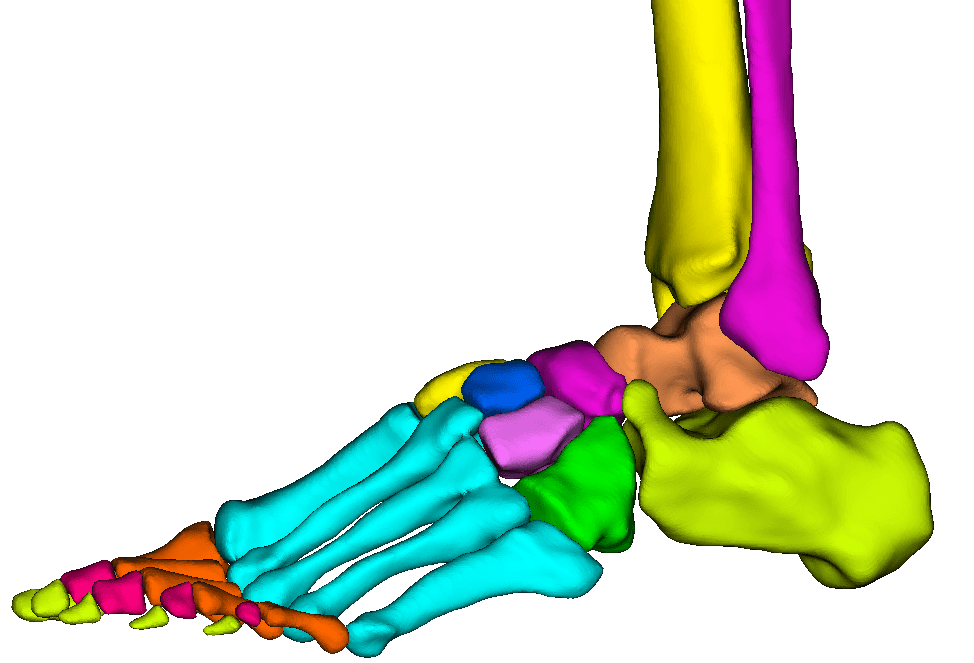

Segment bones, vasculature, and soft tissues with precision. User-friendly tools for accurate anatomical boundary delineation.

Real-time 3D rendering of segmented structures. Create patient-specific anatomical models for visualization and analysis.

Create patient-specific 3D anatomical models for pre-operative planning. Enhance surgical precision and patient outcomes.